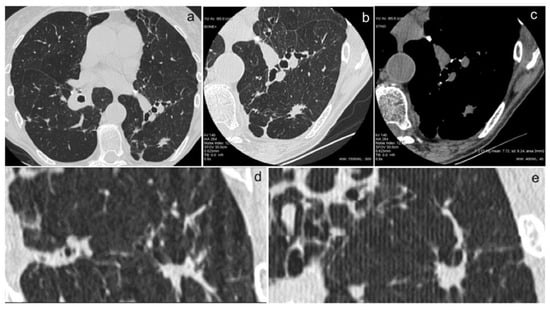

In Figure 1a–d and Figure 2a–e, we show some images from our patients.

Figure 2. (ae). The use of an examination technique with bone plus kernel reconstruction (for the study of lung parenchyma) (a), high spatial resolution (for the study of morphology and margins) (b), and high contrast resolution (for the study of intranodular densities) (c) allow for an accurate characterization of nodular lesions. This type of study makes it possible to obtain images of high diagnostic quality also in coronal (d) and sagittal reconstructions (e), enabling the differential diagnosis of pulmonary nodules.

The results obtained are related to the accurate characterization of nodular lesions through the use of an examination technique with high spatial resolution (for the study of morphology and margins) and high contrast resolution (for the study of intranodular densities). Indeed, this type of study has made it possible to obtain images of high diagnostic quality that facilitate the differential diagnosis of pulmonary nodules in most cases [27]. This study allows for the detection and characterization of ground/glass and especially mixed nodules (solid and ground/glass) for which even the Fleischner Society has developed guidelines for the follow-up of these lesions based on size and composition [28,29,30]. Although several of the analyzed characteristics are already known indicators of malignancy in parenchymal nodules in patients without sarcoidosis (e.g., nodule spiculation and size), the density of the nodule measured with the baseline CT was found to be the most discriminative parameter between sarcoidotic and malignant nodules. This factor, which is currently considered secondary, emerged as fundamentally important in our study.